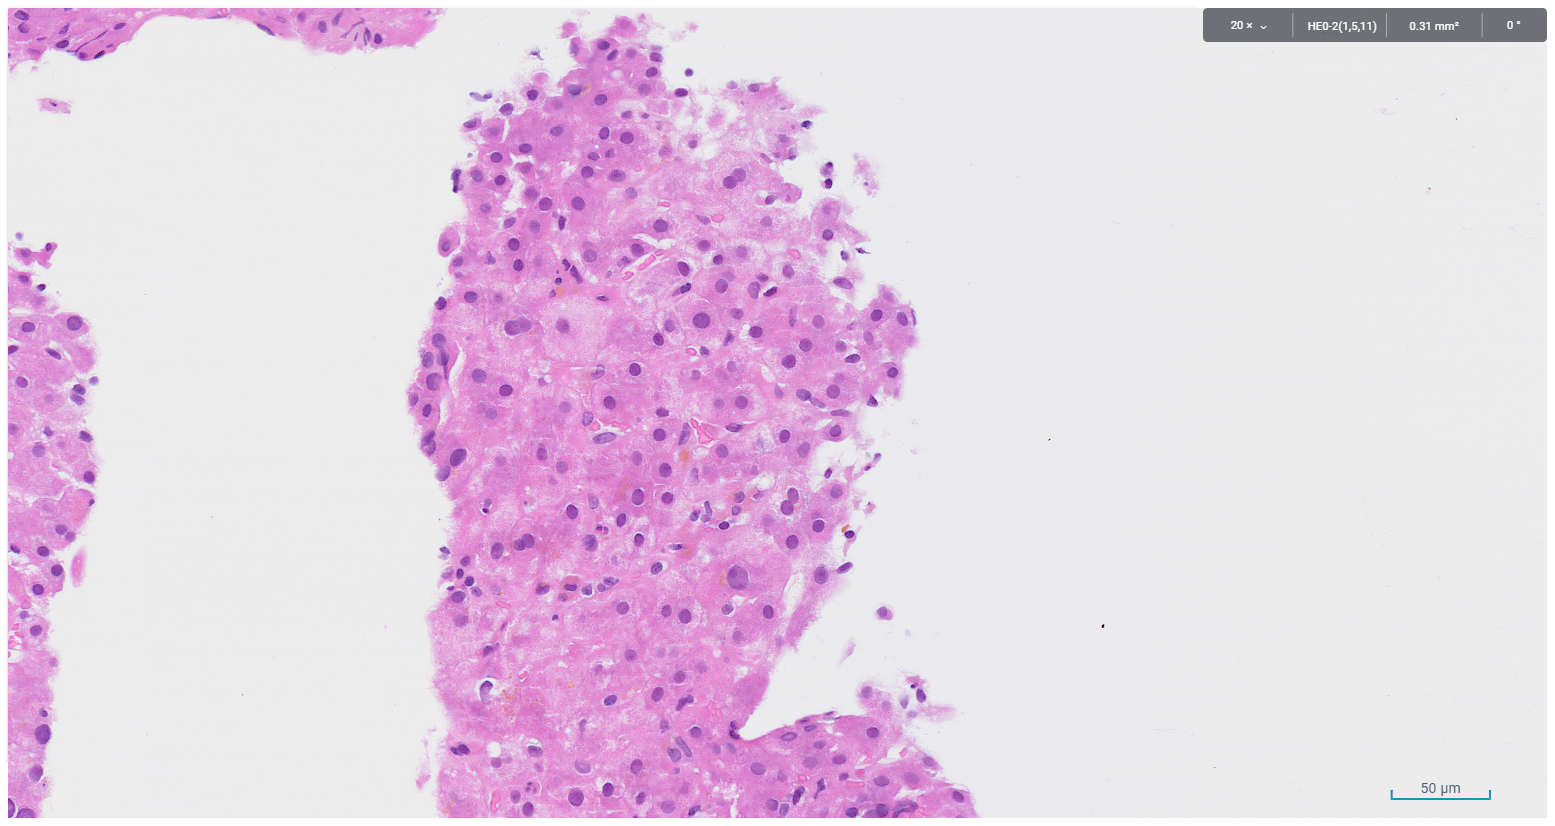

A core biopsy taken from the right hepatic lobe showed periportal chronic inflammation without a prominent plasma cell component, and focal interface activity (Figure 1). Mild bile ductular proliferation and mild periportal fibrosis were noted and highlighted with CK7 immunohistochemistry (Figures 2 and 3). There was no evidence of bile duct injury or ductopenia. The hepatic lobules contained scattered chronic inflammatory infiltrate and mild canalicular cholestasis (Figures 4 and 5). Steatosis, confluent necrosis, Mallory-Denk bodies and granulomata were not identified.

Figure 1. Periportal chronic inflammation devoid of plasma cells, with focal interface activity